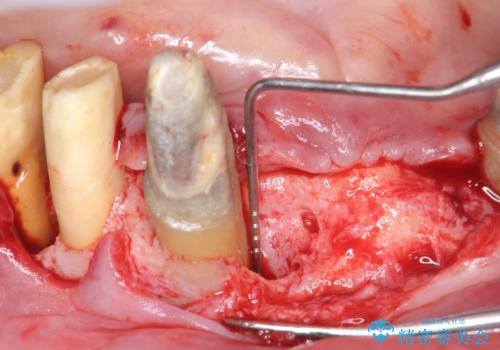

X線検査・視診より強くぶつけた前歯は折れてしまい、抜歯が必要な状況です。

抜歯後の見た目改善として深い咬合関係であることからインプラントは避け、ブリッジで補綴治療を行っていくこととしました。

元々の噛み合わせが深く(ディープバイト)、転んで顎を強打したことで上顎前歯2本が根元から折れてしまい抜歯をしなければいけない状況となってしまいました。